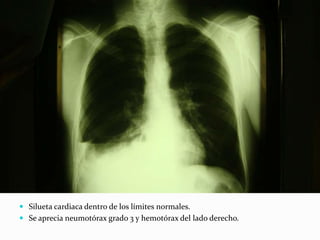

 Silueta cardiaca dentro de los límites normales.

 Se aprecia neumotórax grado 3 y hemotórax del lado derecho.

 Corazón y grandes vasos de configuración normal.

 Seno costodiafragmático derecho, con presencia de líquido.

 Presencia de tubo torácico